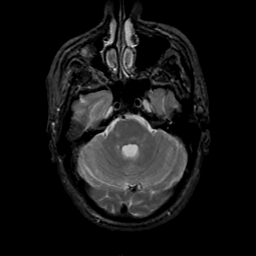

MR Study #18, July 21, 1991 -- Slice #13

[Home][Help][Clinical][Tour 1][Tour 2] Slice 13